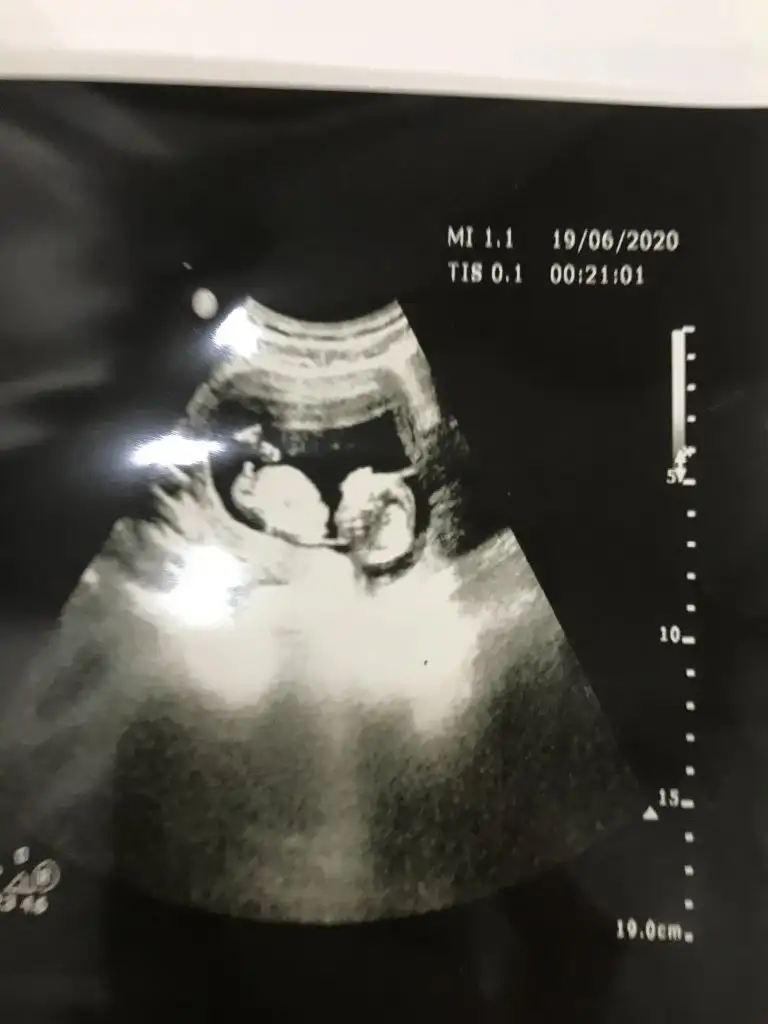

Bunlar net değilBi de bu resimler var.

ÖgrendinizmiEvet net bulamadım en net resmi bu doktor net çekmemiş aslında 12 haftalık teşekkür ederim

Kaç haftalık usg sanki erkek gibi eminde olmadım 11 12 13 haft usgler olmalı tekrar usg paylaşınMerhabalar tahmininizi çok merak ediyorum :)

Üçlü taramada büyük ihtimalle kız olduğu söylendiNet degil usg tek tek çekermisiniz usgler yada başka usg olursa paylaşın 12-13 haftalarda olabilir şimdilik eminde değilim kız gibi gibi emin değilim tekrar usg paylaşın